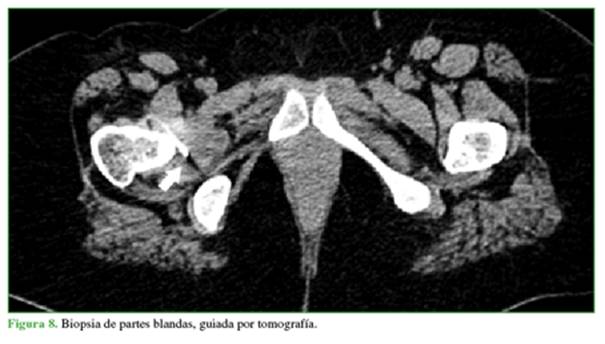

Ante el aumento del componente de partes blandas que rodea el acetábulo, se procedió a tomar una nueva biopsia del plano de los obturadores (Figura 8), con muestras para bacteriología y anatomía patológica.